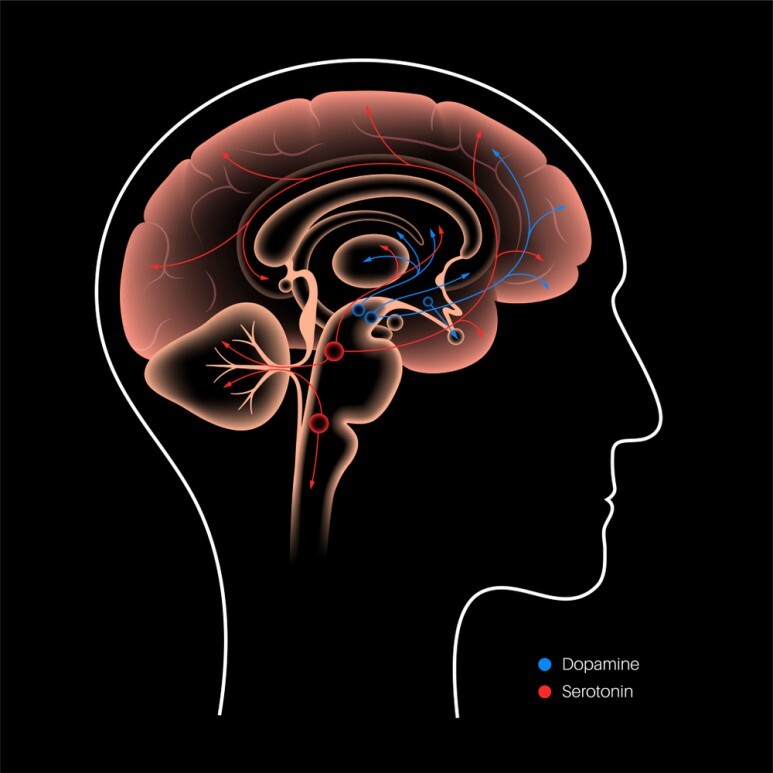

우리의 뇌 속에는 여러가지 신경전달물질이

존재하는데 그 중 운동에 꼭 필요한 호르몬인

'도파민'이 있습니다.

파킨슨병은 이러한 도파민을 분비하는

신경세포가 알 수 없는 원인으로 인해

서서히 소실되어 가는 질환이라고 할 수 있는데요.